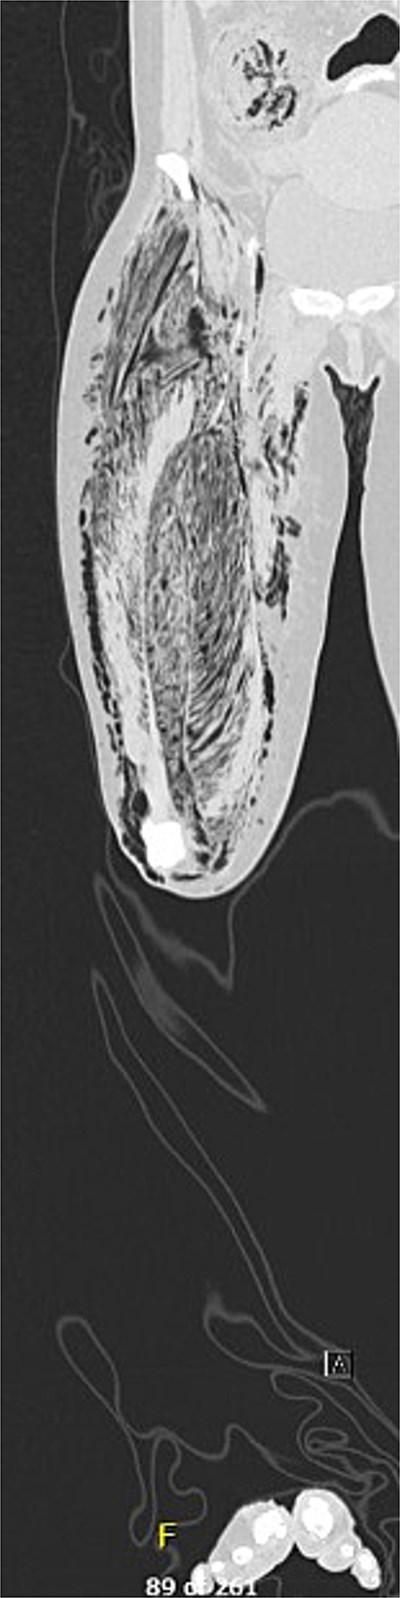

A 50-year-old female with a history of biopsy-proven diffuse large B-cell lymphoma status post induction chemotherapy with Pola-R-CHP (polatuzumab, rituximab, cyclophosphamide, doxorubicin, and prednisone) presented to the emergency department with right lower extremity (RLE) weakness and pain, hypotension, tachycardia, and altered mental status. Physical exam revealed a cool, tense, edematous RLE, with absent distal pulses and no Doppler signals (Fig. 1). Motor strength was severely diminished. Labs were notable for a WBC 1.2 × 103/mcl, hemoglobin 7.6 g/dl, CO2 17 mmol/L, AGAP 24 mmol/L, creatinine 1.73 mg/dl, CRP 35.6 mg/dl, and a LRINEC score of 10. An X-ray of the RLE demonstrated extensive air dissecting superficial, deep, and intramuscular fascial planes. Prior to consultation, a CT (Fig. 2) obtained in the emergency department, demonstrated extensive necrosis of the right thigh, with gas tracking from the iliac vein down to the popliteal vein, into the femoral intramedullary space, and the retroperitoneum. Additionally, diffuse fat stranding and pneumatosis intestinalis were noted in the cecum and terminal ileum.